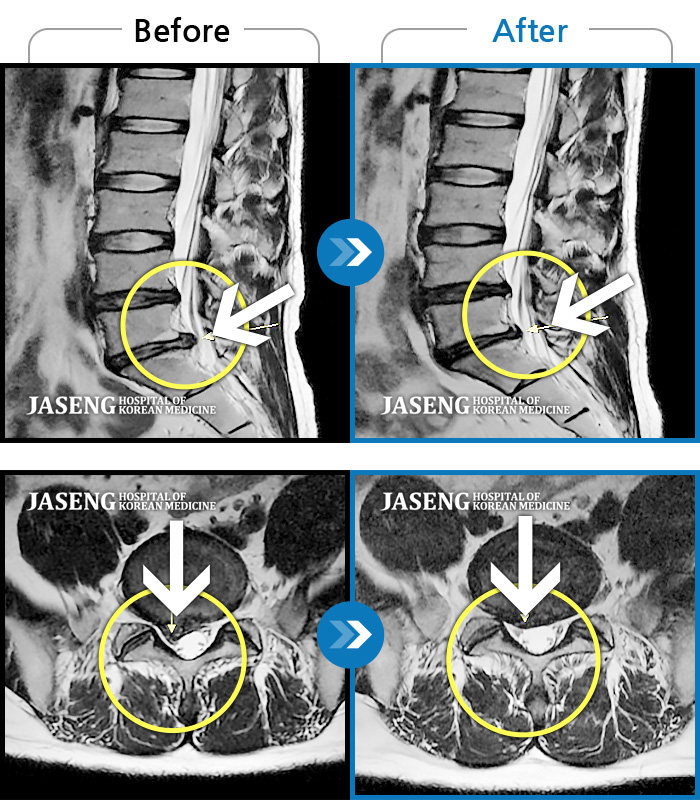

허리디스크

울산 · 정운석 원장

좌측 하지 외측이 저리면서 당김증상 및 감각둔화

촬영시기

2016.12.22 ~ 2022.11.24

2022.12.09